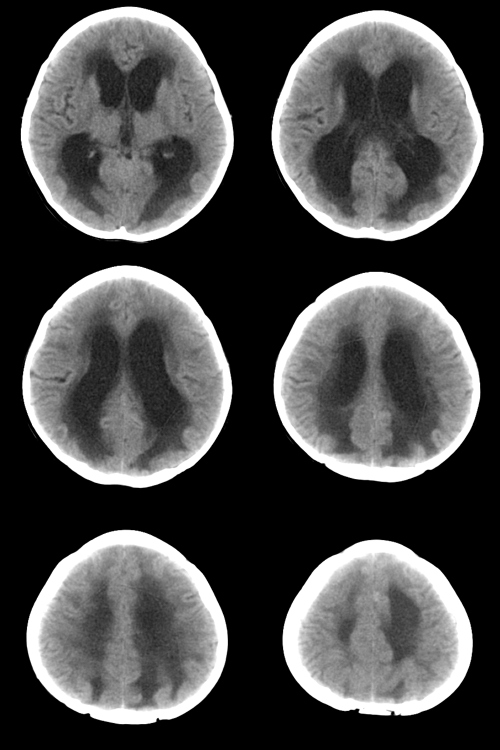

脑积水伴室旁白质水肿

脑积水伴室旁白质水肿!

脑积水伴室旁白质水肿,建议mri 及增强检查

梗阻性脑积水.室旁白质水肿.